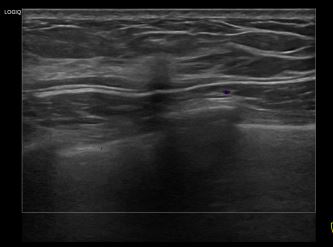

아산유외과개원후 949번째 유방암진단

상기환자는 외부검사 이상소견으로 내원하신 60대 후반 여성분으로 의심스러운 우측 혹 조직검사 시행해 유방암 진단되었습니다